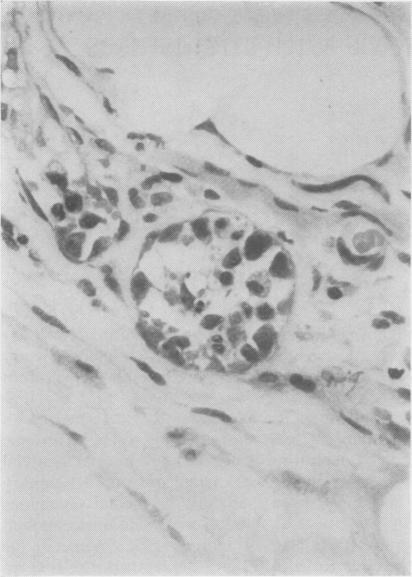

The clinical and pathological findings of a case of systemic angioendotheliomatosis are presented. The previously published cases of this disease are analysed. The present case is only the third to show clear evidence of metastasis.

本文报告了一例系统性血管内皮瘤病的临床及病理表现。对该疾病既往已发表的病例进行了分析。本病例是第三例有明确转移证据的病例。